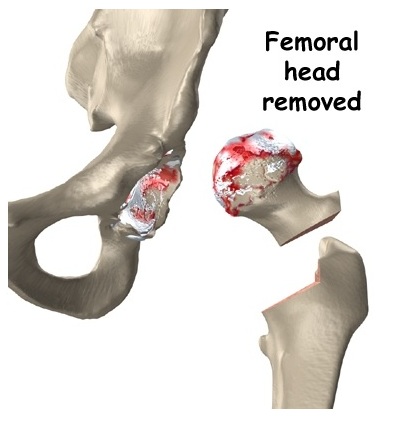

Sau khi rạch da và bóc tách phần mềm, quá trình thay khớp háng gồm các bước cơ bản sau:

Bước 1: Cắt bỏ phần xương và sụn khớp của xương đùi bị tổn thương. Các bác sỹ sẽ cắt bỏ phần chỏm và cổ xương đùi đến gần nền cổ xương đùi.